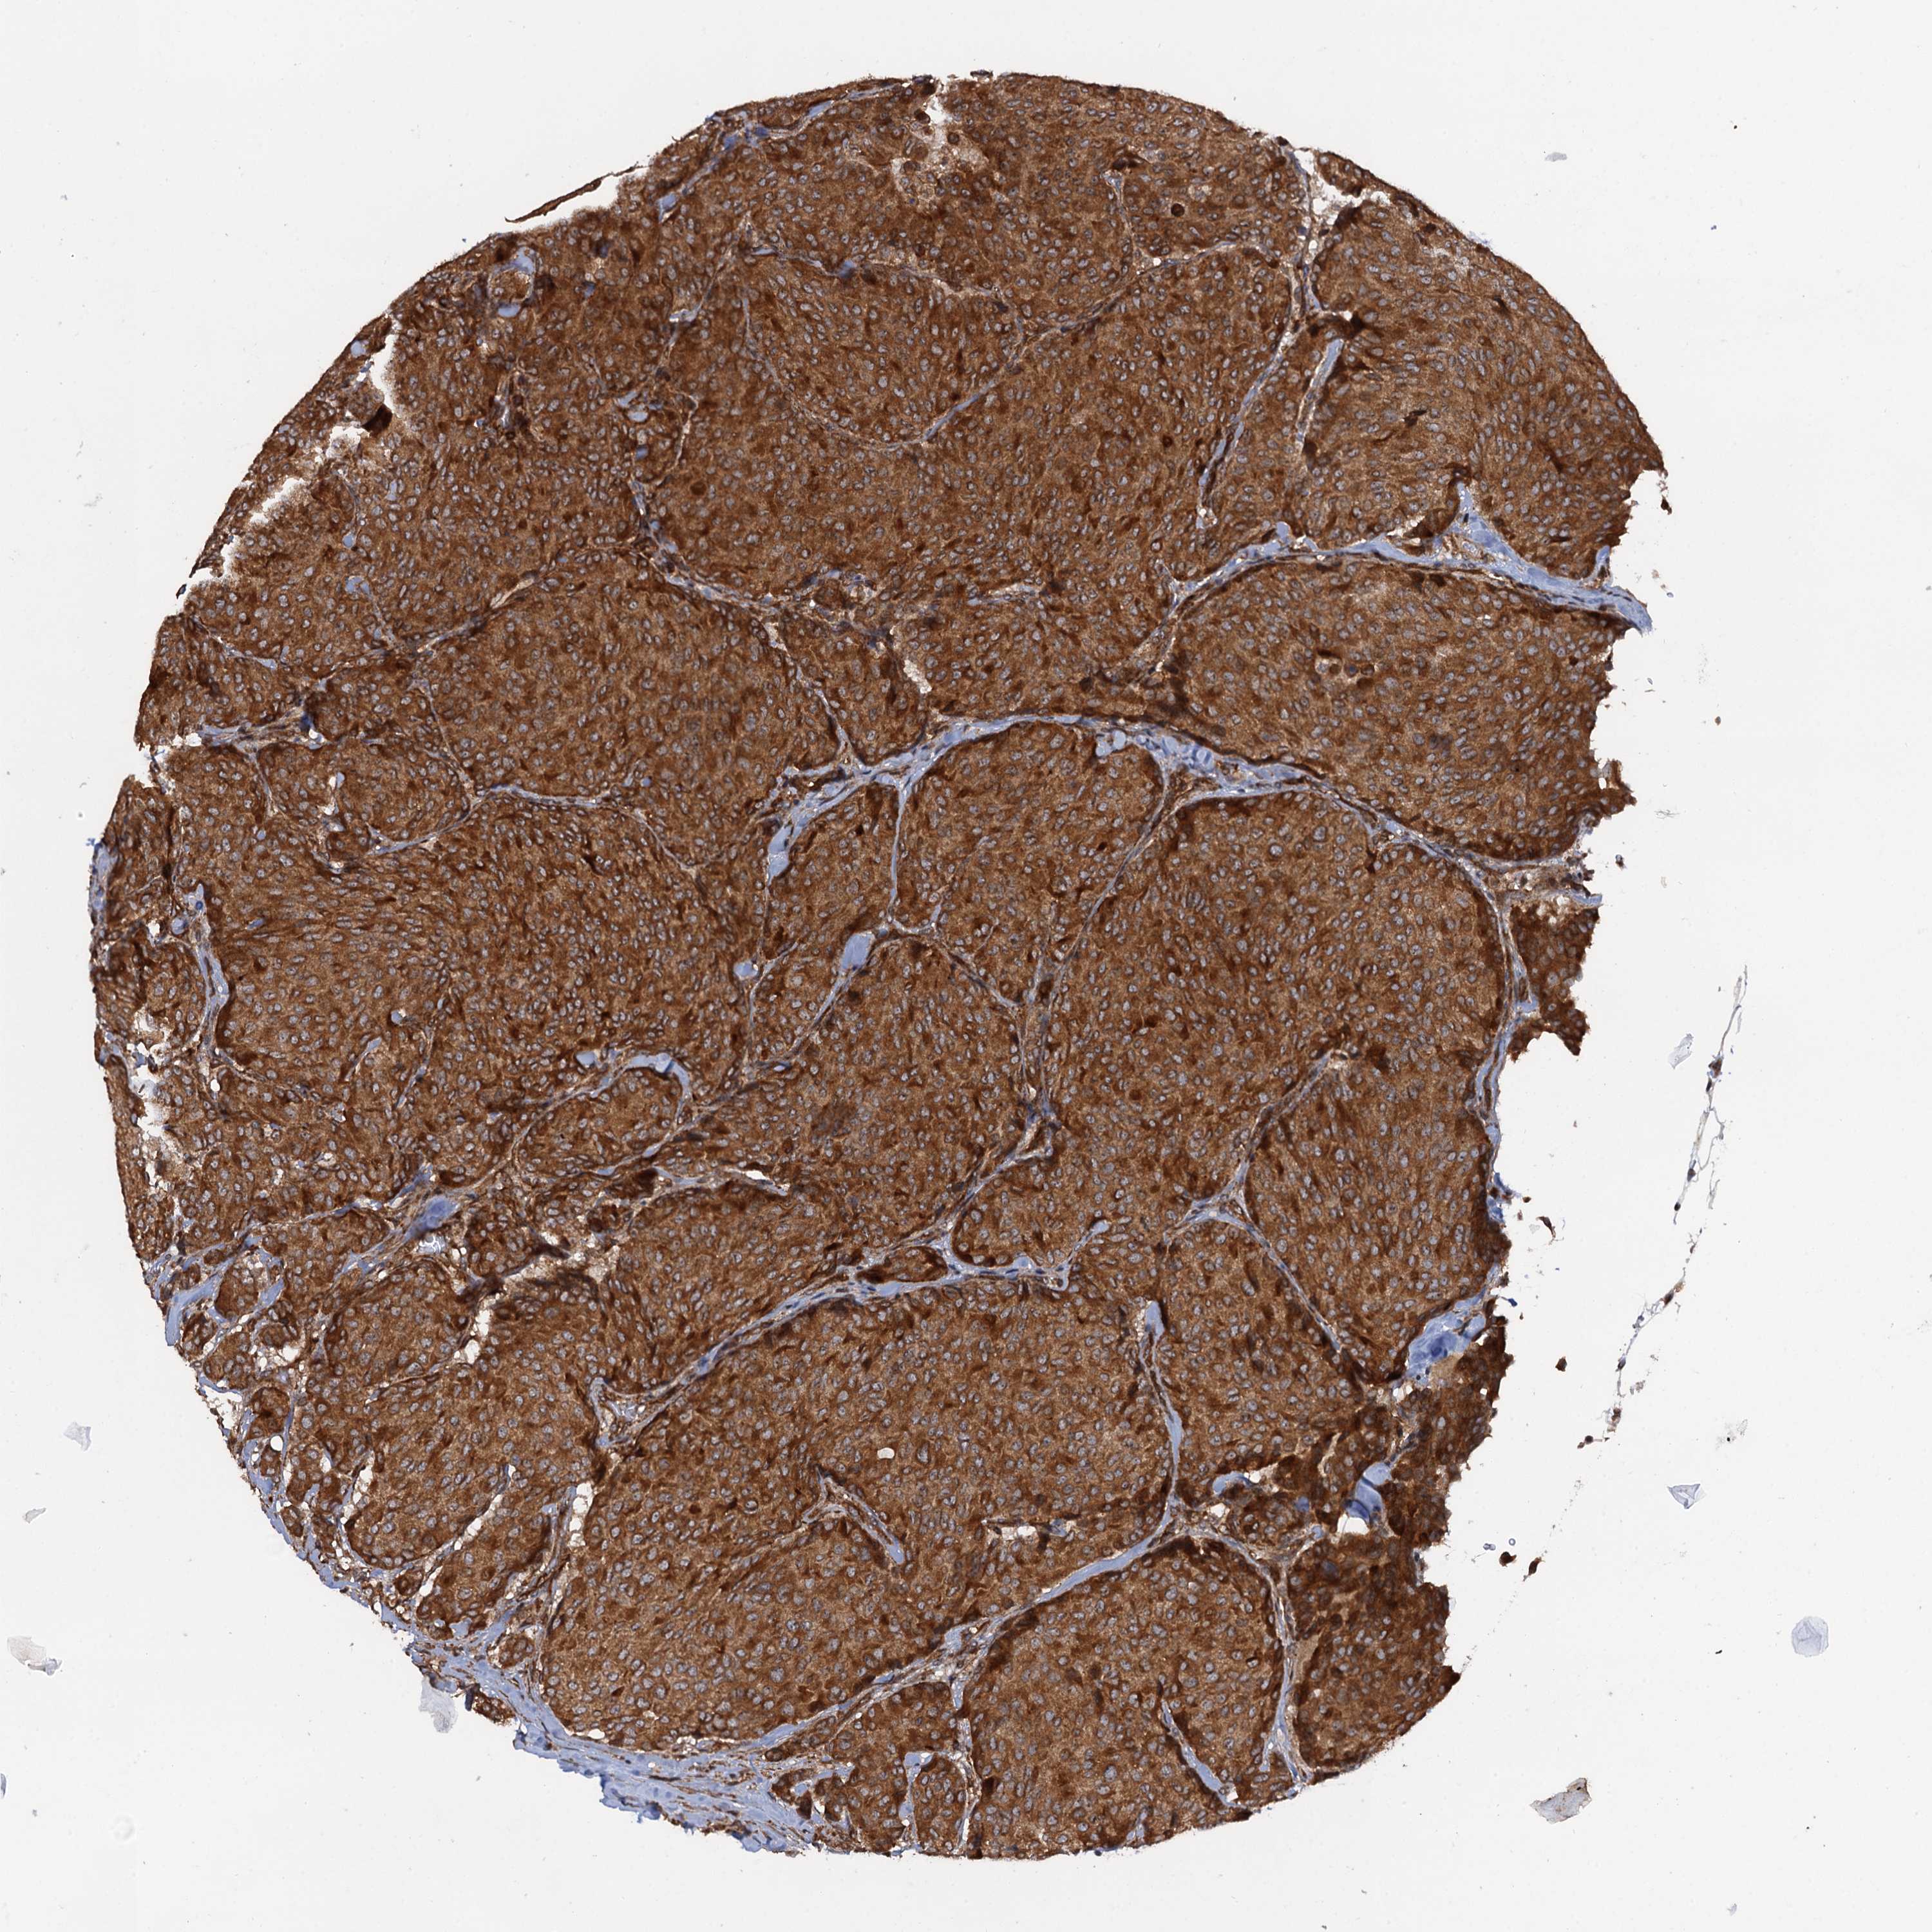

CANCER BREAST CANCER Show tissue menu

BRCA TCGA BRCA VALIDATION PROTEIN EXPRESSION